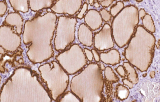

L’immunoistochimica (IHC) con anticorpi primari CE/IVD è essenziale per una diagnosi e classificazione accurata sia delle malignità ginecologiche che mammarie. Questi anticorpi consentono la rilevazione precisa di marcatori tumorali e proteine cellulari, supportando la diagnosi differenziale e guidando strategie terapeutiche personalizzate.

Studi recenti sottolineano il valore diagnostico delle proteine del complesso SWI/SNF, in particolare ARID1B, nell’identificazione di malignità ginecologiche dedifferenziate e indifferenziate – tumori aggressivi con prognosi sfavorevole. L’IHC di ARID1B offre alta specificità e viene sempre più integrata nei pannelli diagnostici per migliorare la precisione. Pannelli con marcatori aggiuntivi supportano anche la differenziazione dei sarcomi uterini, aumentando l’accuratezza diagnostica. Evidenze emergenti suggeriscono che ARID1B potrebbe rappresentare un potenziale bersaglio terapeutico nel carcinoma ovarico a cellule chiare, sebbene le applicazioni cliniche rimangano in fase di ricerca.